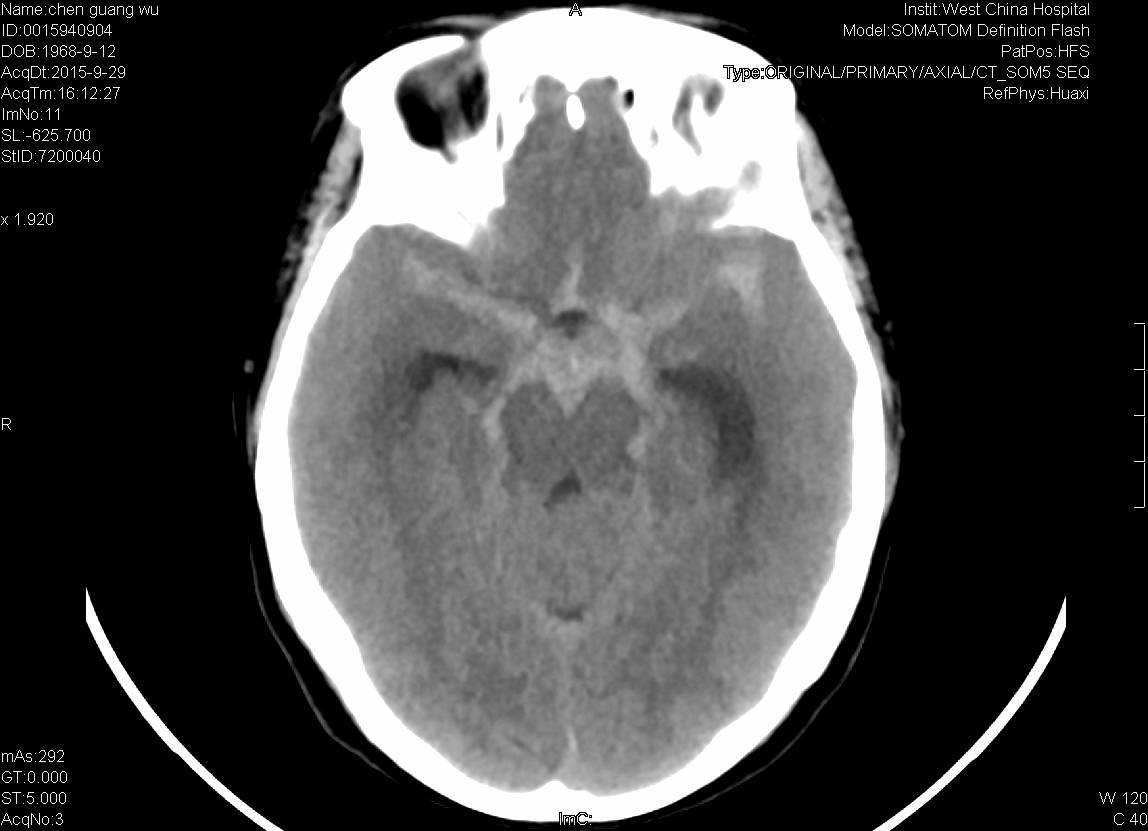

CT:蛛网膜下腔出血。

DSA:基底动脉尖端分叶状小动脉瘤,左侧颈内动脉床突上段动脉瘤。

颈内动脉床突段一约3.5mmx2.75mm囊性显影,动脉瘤。

基底动脉尖1.8mmx3.2mm囊性显影,分叶状动脉瘤。